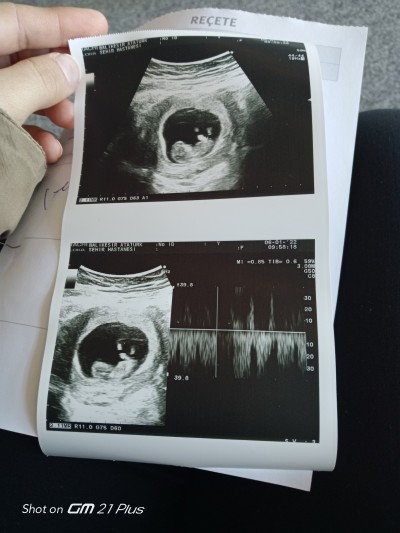

Arkadaslar suan 11 haftalik dusuk riski geçirdik dualarınızı bekliyoruz sizce cinsiyeti nedir❤️

image.

Gebelik haftası 11+1